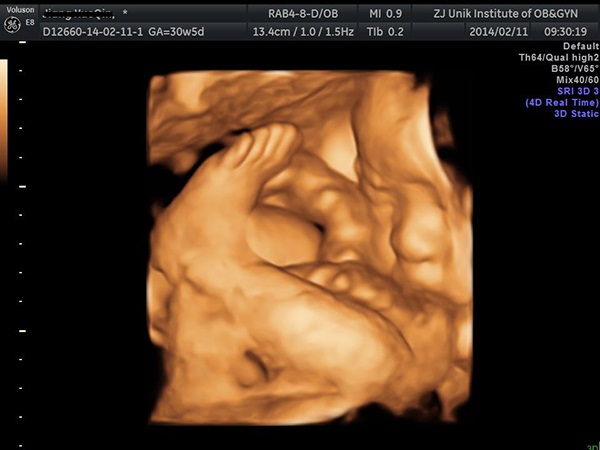

四维彩超是孕期非常重要的一项检查,能够胎儿是否存在畸形,进一步了解胎儿的健康状况。四维彩超一般是在女性怀孕5-6个月的时候做,这个时候胎儿的生殖器官已经发育完全,所以通过四维是能够准确判断胎儿是男是女的。但是由于我国禁止胎儿性别的鉴定,所以医生是不会告知的,但是很多网友发现通过四维彩超单子也是可以判断胎儿性别的,单子上m和f就可看男女,如果单子上的是m就说明是男宝宝,f就说明是女宝宝,但是具体准不准就不一定了。

很多人认为通过四维彩超单上的数据和信息也是可以判断胎儿的性别的,像是四维单子上的m和f、英语字母Qual high 、孩子腿部间的形状、孕囊的大小等都是可以用于判断生男生女的。其中,通过单子上的m和f看男女是最简单的,但其实四维彩超单中的F和M两个英文字母和胎儿性别是没有关系的,M与F只不过孕期产检时一般的纪录简称而已,所以建议大家也不要太过相信。

1在四维单子的顶部最右侧有二行字,由英语字母和数字构成,假如第一行是M开始,那就是male男的意思,就是怀的是男孩的意思,如果是F开始便是female女的意思,也就是怀女宝宝的意思;2四维彩超单中单子中英语字母也是可以判断胎儿性别的,一般认为Qual high 1是就是生女孩的意思,2则是生男孩儿的;3彩超单子上胎儿的腿部间特点也可以判断胎儿性别,如果腿部间有尖尖的亮点,那就是男孩,如果腿部间有三条白线,那就是女孩;4四维单子上的如果孕囊的长和宽相差在一倍以上,那就怀的就是男孩,长和宽相差不大的话,怀的就是女孩。

四维单子上m和f看男女的方法其实并不是很准,因为彩超单子上的m和f就是非常普通的产检记录简称,脸部先露位置即是“颏”(简称为M),和胎儿是男是女是没有任何关系的,所以通过这种方法判断生男生女是不可靠的,建议大家不要盲目相信。